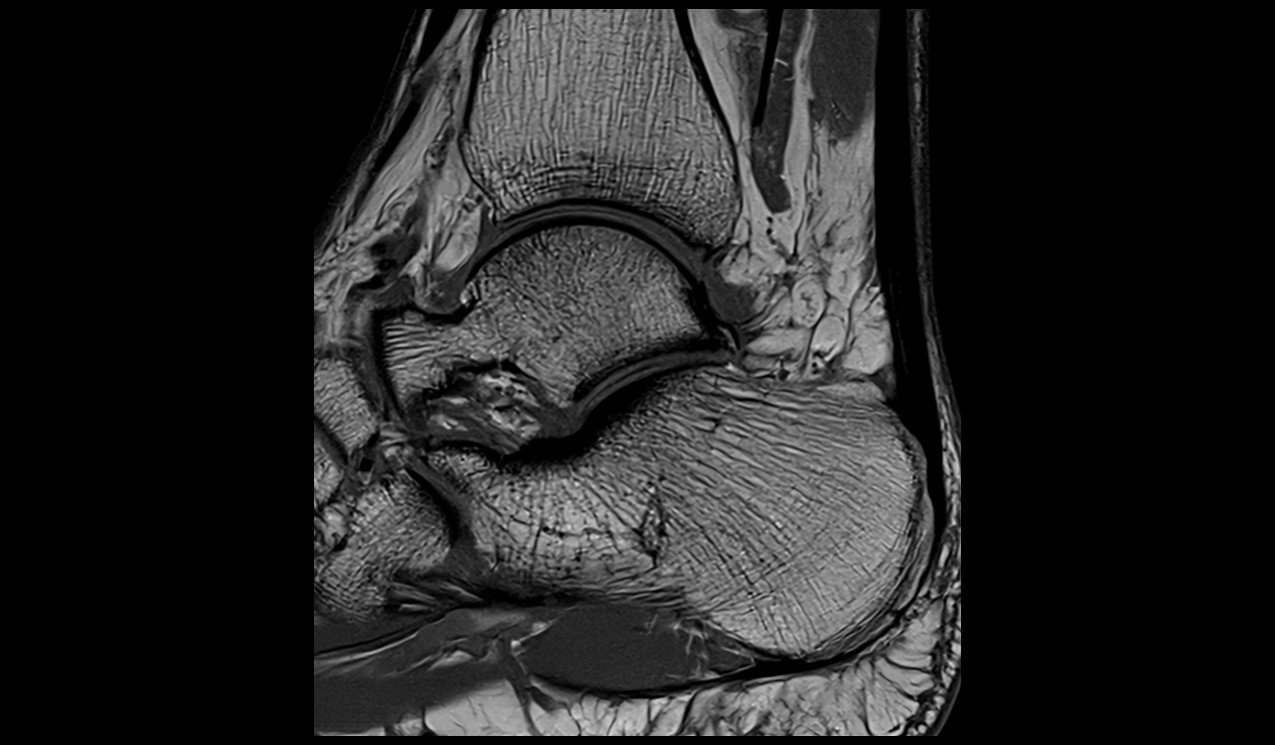

Ankle MRI sagittal t1 image